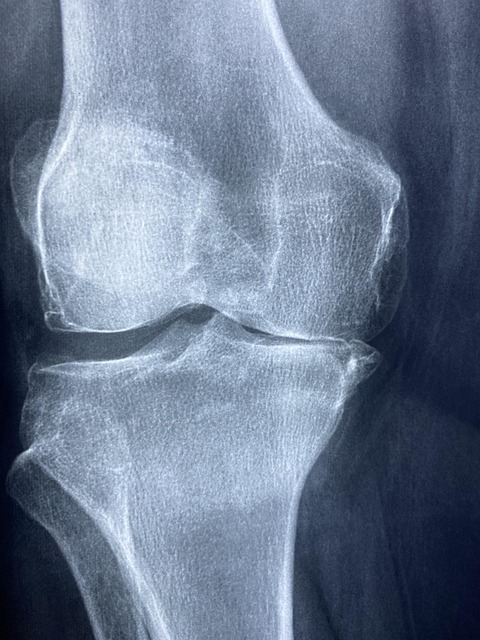

관절은 뼈와 뼈가 연결되는 부분으로, 움직임을 가능하게 해줍니다. 이 부분은 연골, 관절액, 인대, 힘줄 등 여러 구조물로 이루어져 있습니다. 연골은 뼈와 뼈 사이에서 충격을 흡수하고, 관절액은 윤활 작용을 통해 관절의 움직임을 도와줍니다.

관절은 우리 몸이 자유롭게 움직이도록 해주는 중요한 부분이기 때문에, 그 구조와 기능을 이해하는 것은 관절 건강을 지키기 위한 첫걸음입니다. 관절의 건강 상태는 우리의 삶의 질에 반영되며, 이를 통해 우리 몸의 전반적인 건강에도 긍정적인 영향을 미칠 수 있습니다.

관절 건강을 사전에 관리하기 위해서는 정기적인 건강 검진이 필요합니다. 조기에 관절 문제를 발견하면 적절한 치료를 받을 수 있으며, 심각한 질환으로 악화되는 것을 방지할 수 있습니다.

특히 관절 염증이나 통증이 느껴지는 경우, 신속하게 의료 전문가와 상담하여 진단을 받고 적절한 치료를 진행하는 것이 중요합니다. 이를 통해 건강한 관절을 오래도록 유지할 수 있습니다.